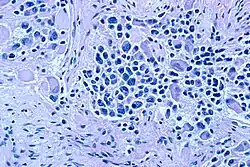

| Microscopic view of a typical neuroblastoma with rosette formation | |

On microscopy, the tumor cells are typically described as small, round and blue, and rosette patterns (Homer Wright pseudorosettes) may be seen. Homer Wright pseudorosettes are tumor cells around the neuropil, not to be confused with a true rosettes, which are tumor cells around an empty lumen.[29] They are also distinct from the pseudorosettes of an ependymoma which consist of tumor cells with glial fibrillary acidic protein (GFAP)–positive processes tapering off toward a blood vessel (thus a combination of the two).[30] A variety of immunohistochemical stains are used by pathologists to distinguish neuroblastomas from histological mimics, such as rhabdomyosarcoma, Ewing's sarcoma, lymphoma and Wilms' tumor.[31]

Neuroblastoma is one of the peripheral neuroblastic tumors (pNTs) that have similar origins and show a wide pattern of differentiation ranging from benign ganglioneuroma to stroma-rich ganglioneuroblastoma with neuroblastic cells intermixed or in nodules, to highly malignant neuroblastoma. This distinction in the pre-treatment tumor pathology is an important prognostic factor, along with age and mitosis-karyorrhexis index (MKI). This pathology classification system (the Shimada system) describes "favorable" and "unfavorable" tumors by the International Neuroblastoma Pathology Committee (INPC) which was established in 1999 and revised in 2003.[32]